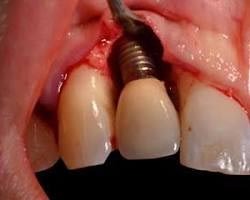

Implant de dentaire définition

Un implant dentaire est une racine artificielle, généralement en titane, insérée dans l’os de la mâchoire pour remplacer une dent manquante. Il sert de support stable à une couronne, un bridge ou une prothèse, restaurant fonction masticatoire, esthétique et confort durablement.